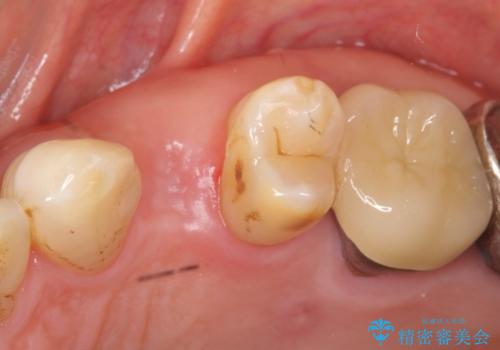

歯がわれた 抜歯してインプラント 50代男性

- 歯ぐきの腫れと痛みを主訴に来院された患者様です。

精査したところ、歯が割れており保存不可能な状態であったためやむなく抜歯しました。

患者様のご希望によりインプラント治療を行いました。